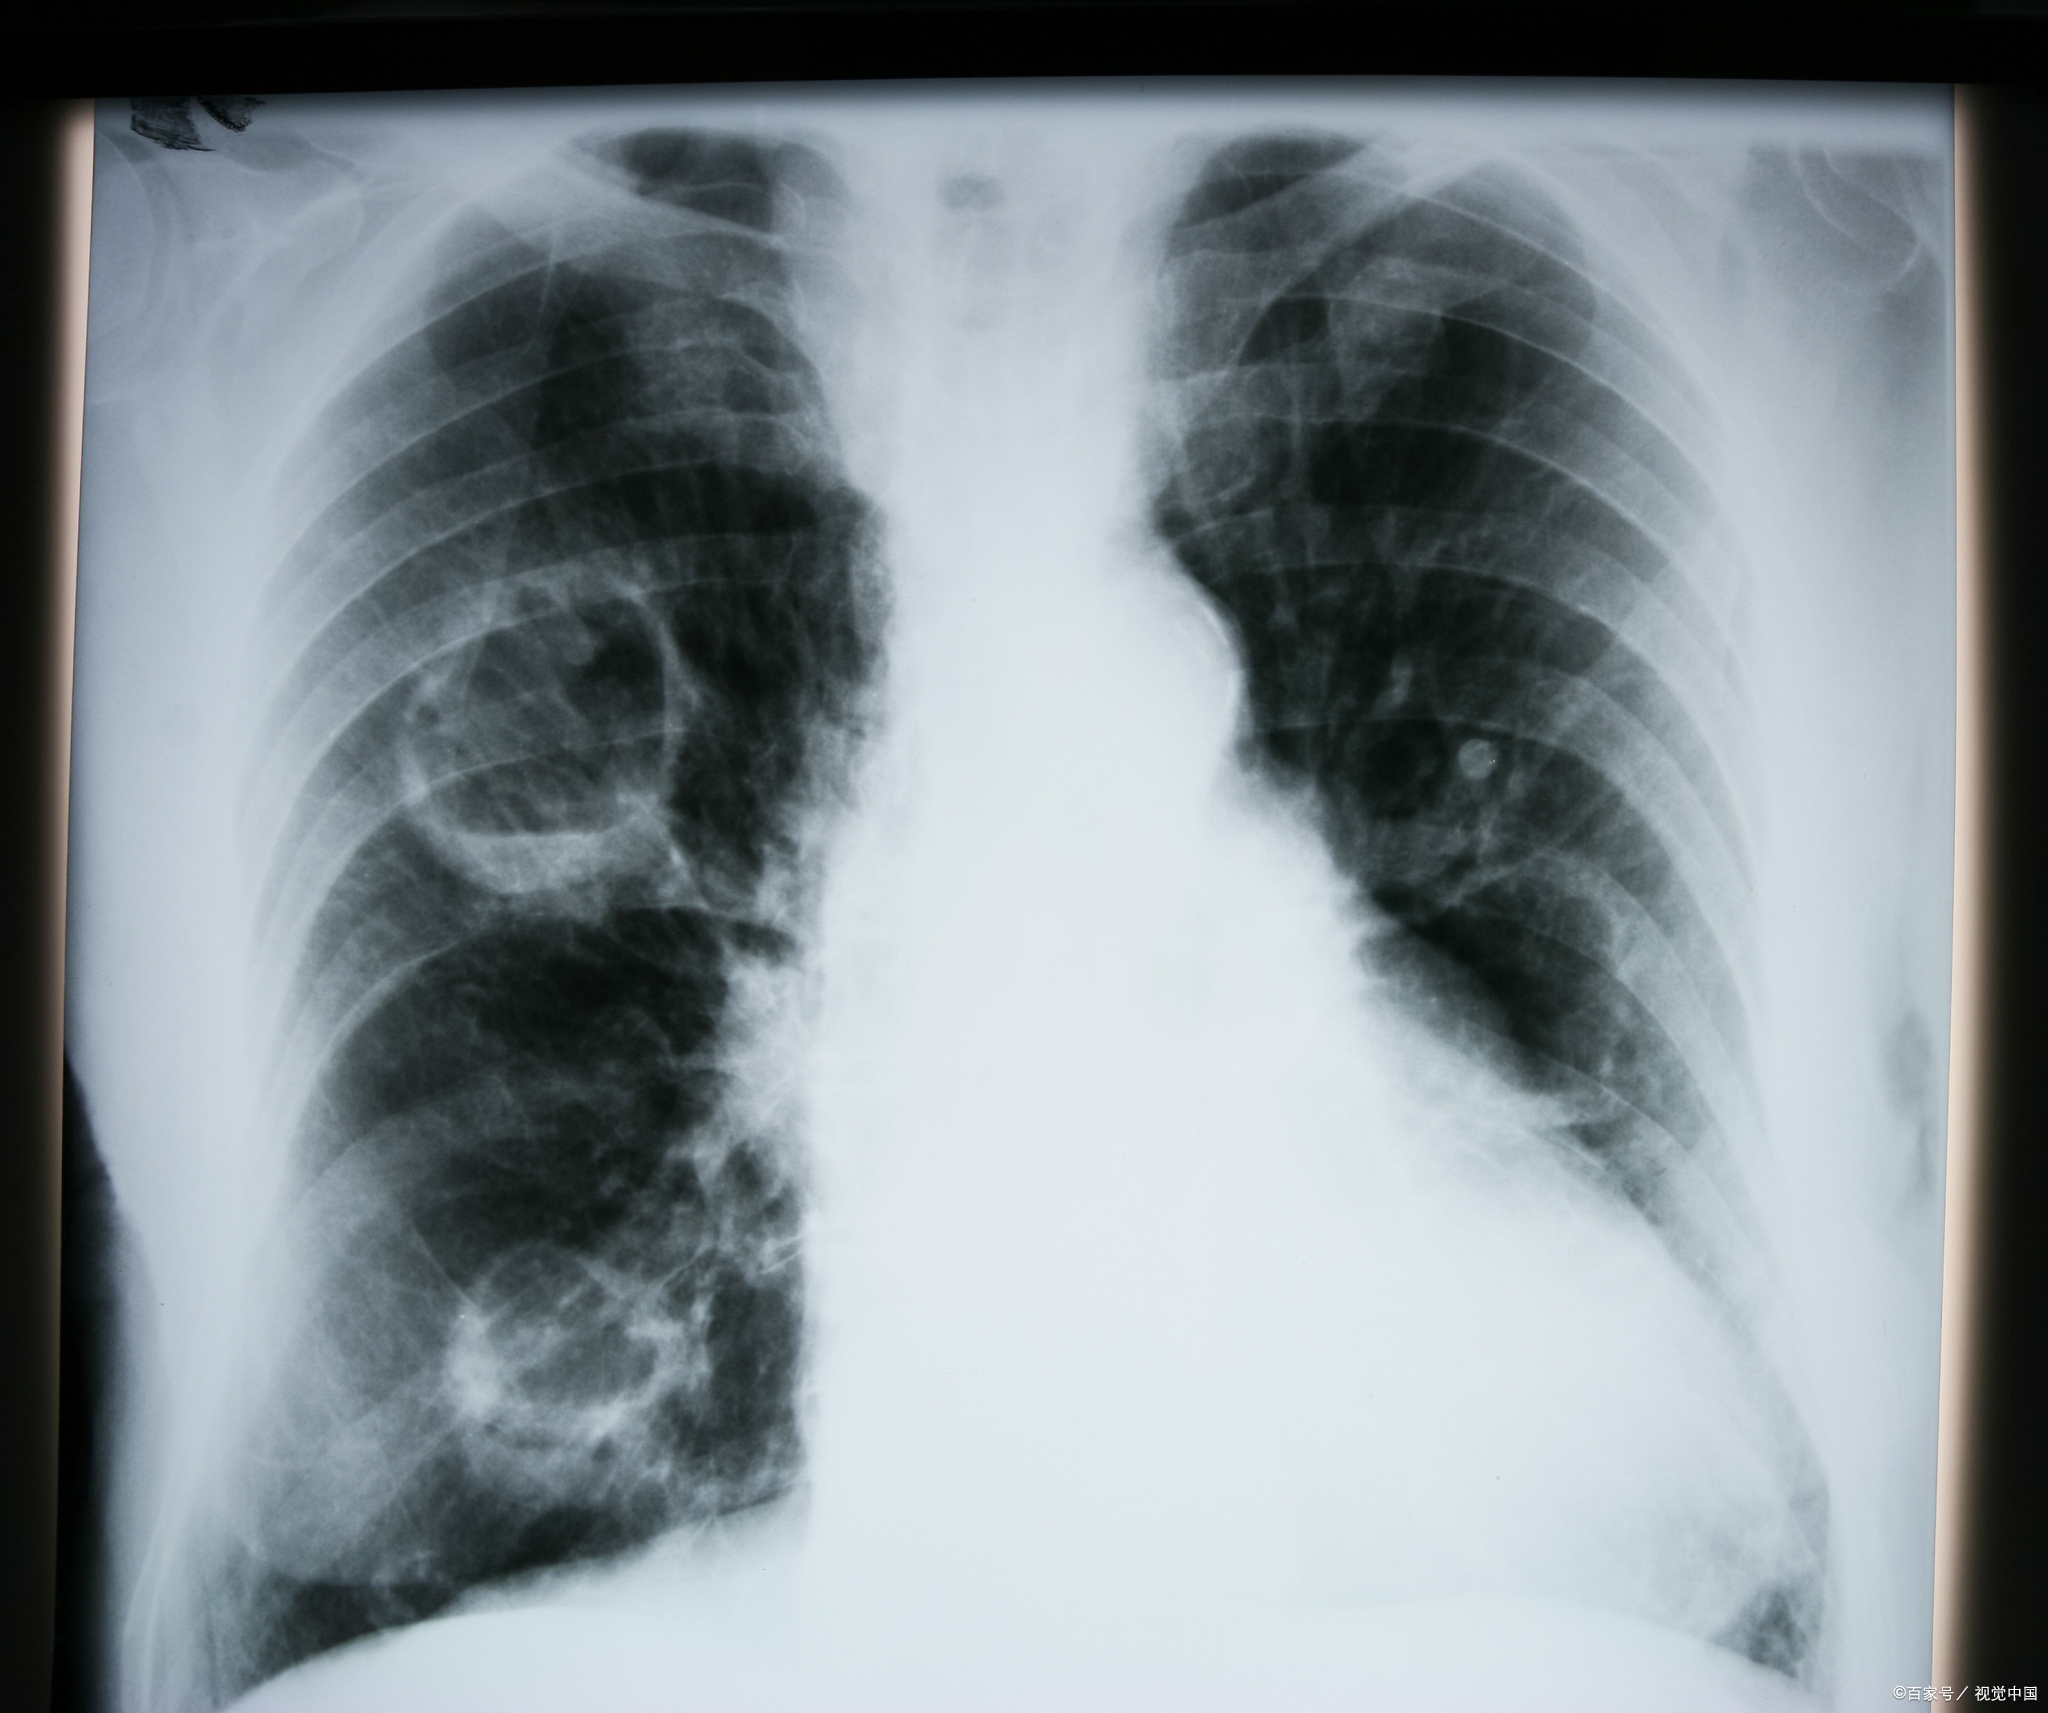

论肺ct的重要性,最近大叶性肺炎,重症肺炎多见,下图胸片对比右侧相对

大叶性肺炎是一种在远端气腔内发展的炎性病变,具有其独特的特点

肺炎克雷伯杆菌感染影像学表现